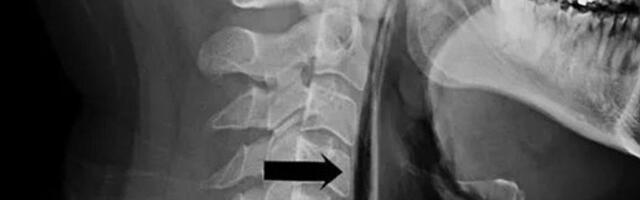

319 Правдива ли новость про жителя Карелии, который разорвал глотку, пока пытался не чихнуть?

Правдива ли новость про жителя Карелии, который разорвал глотку, пока пытался не чихнуть?